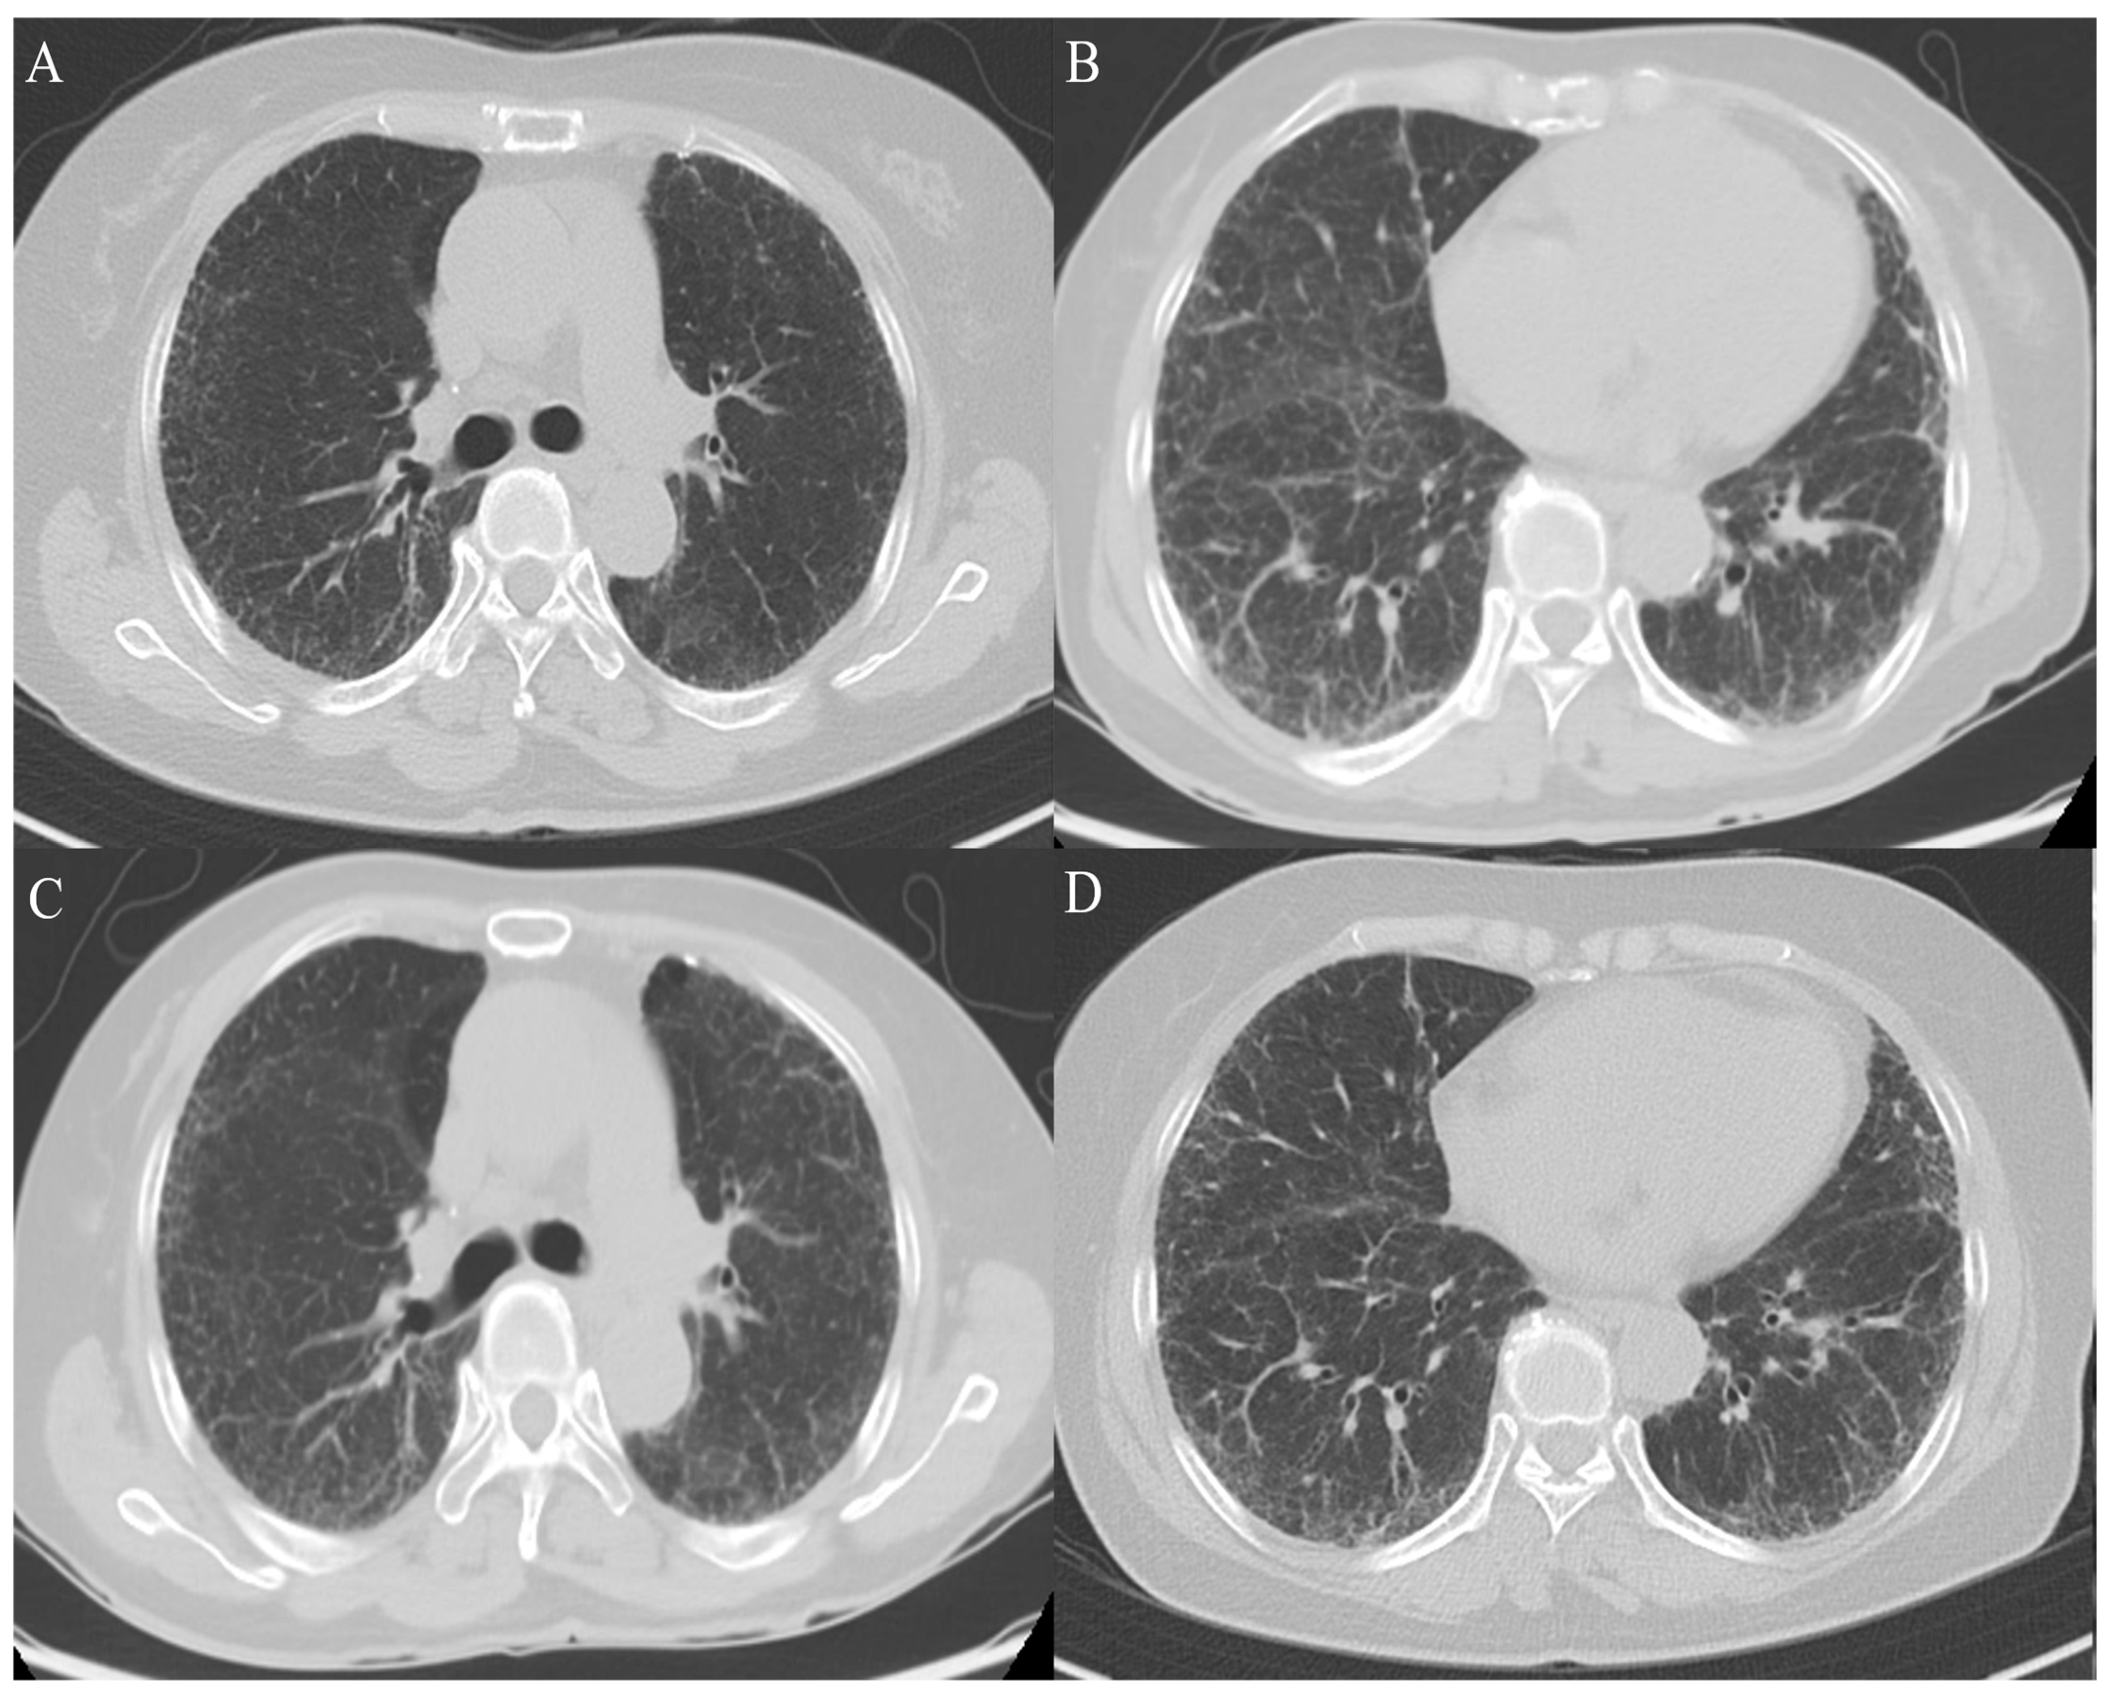

In October 2023, due to ongoing symptoms, the patient was evaluated at the ILD center at Haeundae Paik Hospital in the Republic of Korea. No evidence of pulmonary thromboembolism (PTE) or significant progression of the usual interstitial pneumonia was observed on the chest computed tomography (CT) scan (Figure 1). The PFT revealed a forced vital capacity (FVC) of 2.11 L (69% predicted) and a diffusing capacity for carbon monoxide (DLco) of 3.9 mL/min/mmHg (22% predicted), indicating a disproportionate decline in DLco relative to FVC. Ultimately, due to suspicions of PH-ILD progression, we elected to conduct RHC. A repeat RHC revealed a decreased PVR of 13.78 WU, but an increased mPAP of 62 mmHg and a PCWP of 11 mmHg. We considered administering inhaled treprostinil for PH-ILD. Based on the test results, considering the possibility of a pulmonary vascular phenotype PH-ILD, the patient commenced treatment with inhaled iloprost (Ventavis®) at 10 mcg every six hours.

Figure 1. Disease status of IPF over time. A comparison between CT images from 6 October 2022 (A,B) and 17 October 2023 (C,D) shows no significant differences. IPF, idiopathic pulmonary fibrosis; CT, computed tomography.